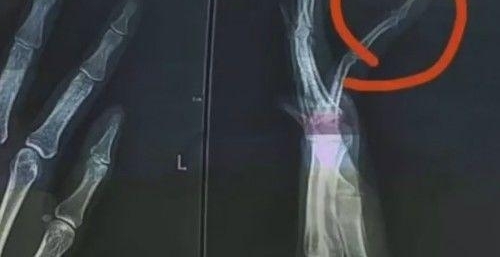

事情发生在11月3日,浙江省杭州市的一小区内。当事人徐女士带着两个孩子散步时,遇到金某和女友未拴狗绳遛狗。因金某小狗追逐小孩,双方发生了争执,金某多次殴打徐女士,当时群众已将其劝离,但是金某又回来打徐女士,最终导致徐女士手指骨折,或留下后遗症.